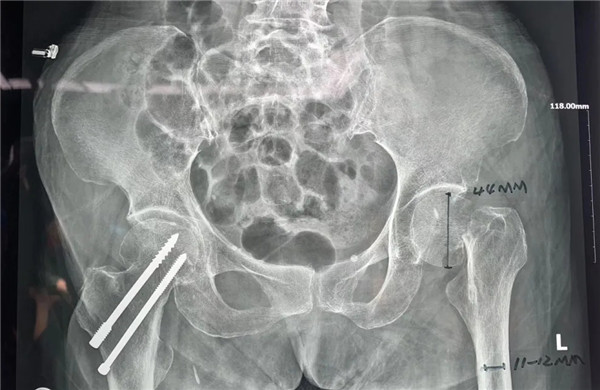

家人趕快第一時(shí)間將她送至我院,經(jīng)拍片后診斷為:左髖股骨頸頭下型骨折,病人入住關(guān)節(jié)科病區(qū)。

確定手術(shù)后,經(jīng)內(nèi)科、麻醉科、超聲科等專家會診后,王老太太符合手術(shù)指征,3月5日,老太太接受了股骨頭置換手術(shù)。

手術(shù)由危立軍副院長主刀,用最少的時(shí)間完成人工關(guān)節(jié)置換,從劃刀到假體安裝好僅僅10分鐘。術(shù)后王老太太一天天好轉(zhuǎn)起來,現(xiàn)已下地康復(fù)行走,臉上洋溢開心的笑容。